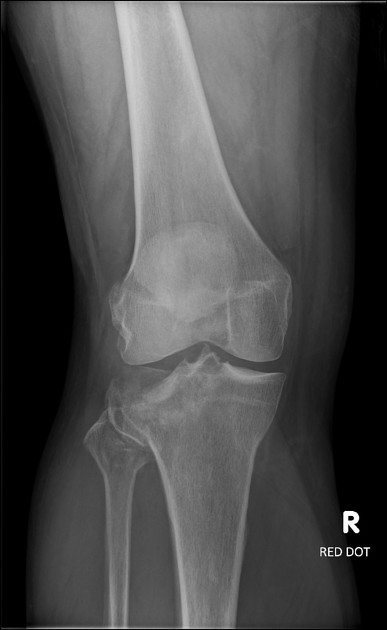

“On initial inspection, there appears to be a fracture of the head of the fibula, but I will proceed to go through it systematically.”

B – Looking at the bones first, there is a fracture in the fibular head. It is a closed, simple, transverse fracture. There is no angulation of the distal segment compared to the proximal, no translation, rotation or shortening. There are no other fractures.

There are no obvious dislocations and the no abnormality in the texture of the bones

D – There are no degenerative changes in the joint spaces

In summary, this film shows a fracture of fibular head which is undisplaced.

Fibular Head Fracture

Image 1: Patel, M. Fibular head fracture. Case study, Radiopaedia.org. https://doi.org/10.53347/rID-19493